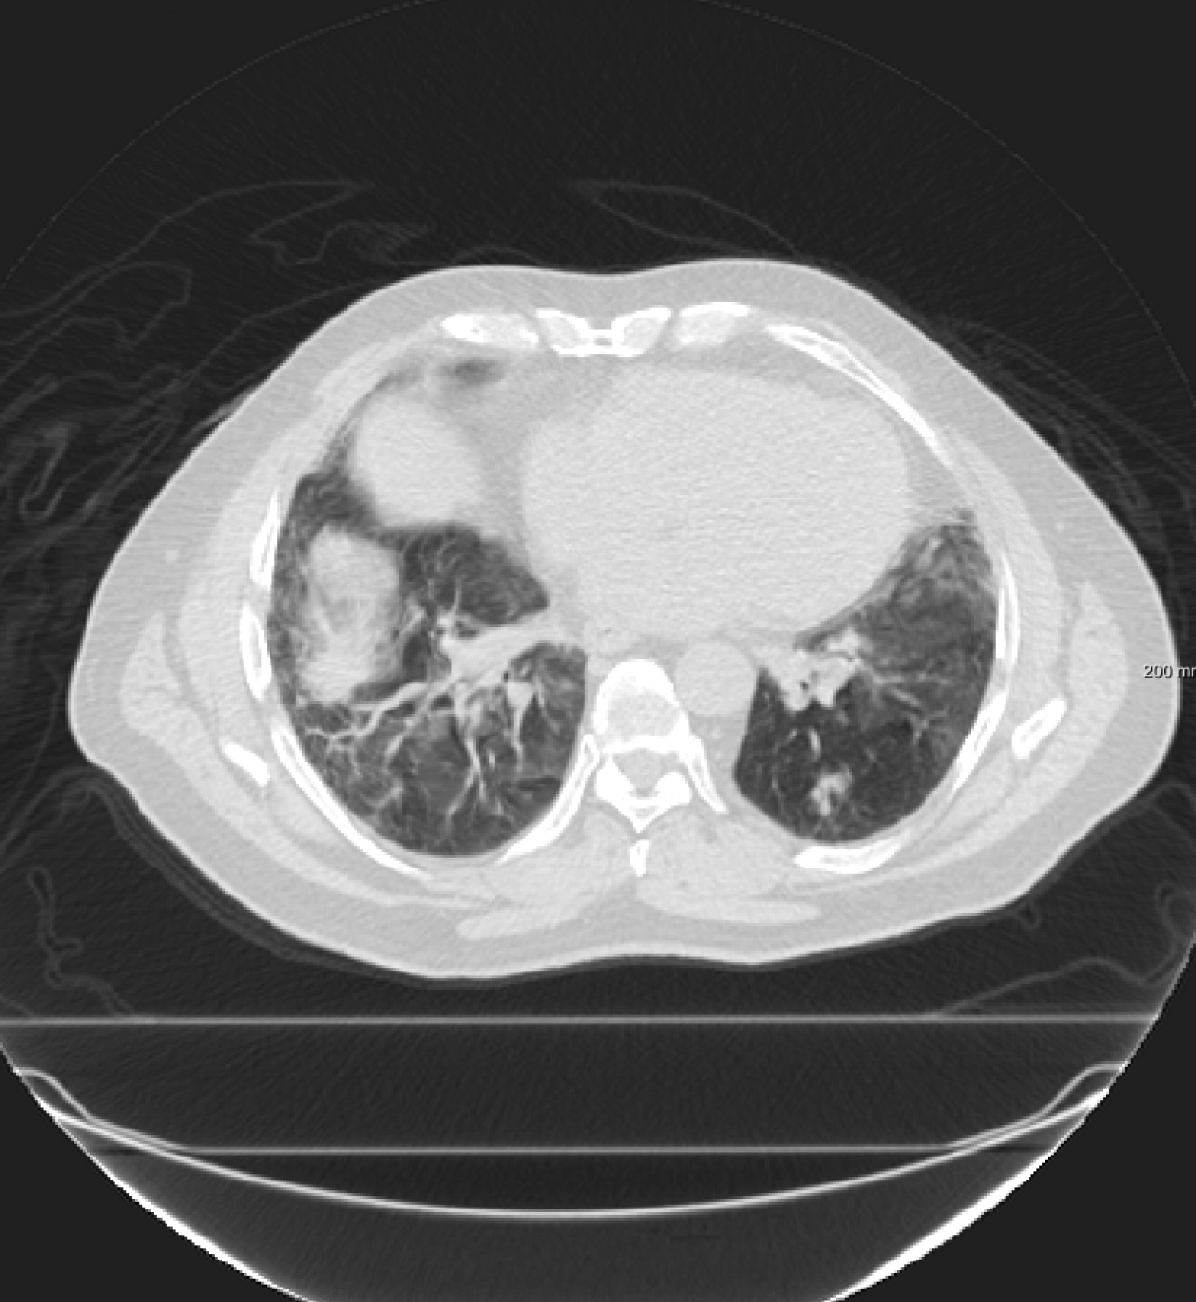

For the DIR-Lab-4DCT database, a comparison between RegNet and affine, B-spline (three resolutions), an advanced conventional registration method using sliding motion (Berendsen et al., 2014) and three other CNN-based methods (Eppenhof and Pluim, 2018; de Vos et al., 2019; Sentker et al., 2018) is available in Table IV. It can be seen that training with “S+M” improved performance slightly with respect to just “S”. Adding the respiratory motion category improved performance substantially, as these are inhale-exhale pairs; this is predominantly caused by the patients where the TRE after affine registration was still quite large. An example visualization is also available in Fig. 5(f), showing that adding the respiratory motion category can align images better in the diaphragm region. The advanced conventional registration method that leverages sliding motion (Berendsen et al., 2014) is still better than RegNet. Note that RegNet was not trained on the DIR-Lab-4DCT data, similar to Eppenhof and Pluim (2018); Sentker et al. (2018). However, de Vos et al. (2019) and Eppenhof and Pluim (2018)-DIR methods were trained on the same database but using cross-validation to report the results. Also note that the results reported in Sentker et al. (2018) are averaged over all phases of DIR-Lab-4DCT (T00 to T10), while the results of other CNN methods (including RegNet) are reported between the maximum inhale and maximum exhale phase (T00 and T50). These reported results are therefore likely somewhat better than the results for T00 and T50 only.